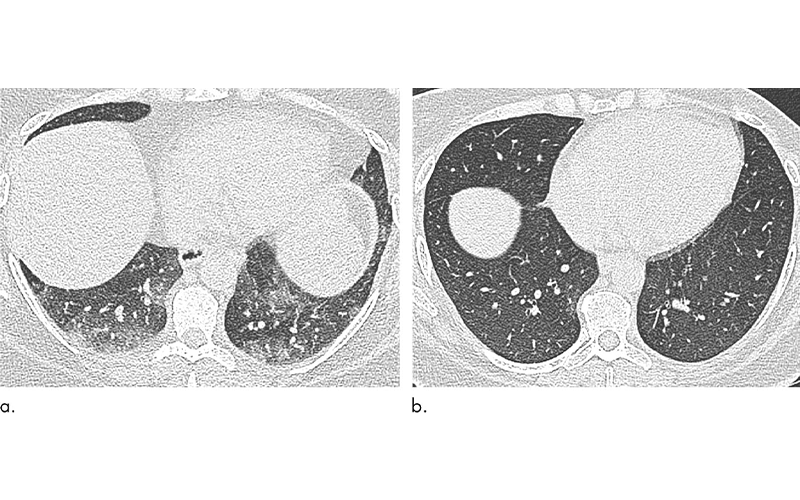

When the researchers compared results at baseline and six months after bariatric surgery, they found that surgery and weight loss were associated with morphological changes to the lung and trachea.

Post-surgery CT showed reductions in air trapping and a lower incidence of tracheal collapse. Change in the extent of CT air trapping was the strongest predictor of improvement in dyspnea.

“For the first time, this study has demonstrated changes in the CT morphology of large and small airways that improve when individuals lose weight,” Dr. Copley said. “These features correlate with an improvement in patient symptoms.”